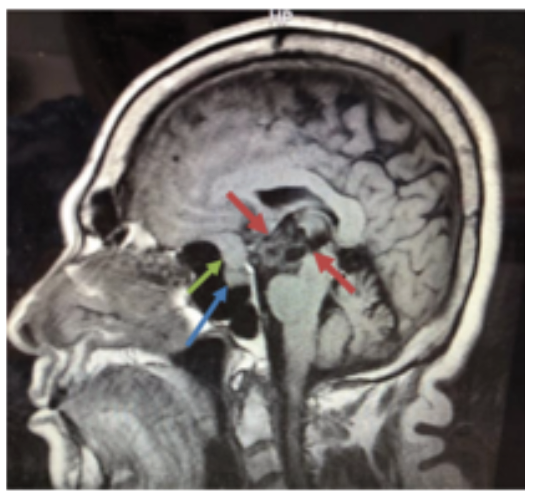

La evolución del paciente fue satisfactoria evidenciándose una franca mejoría de la conducta y de la memoria reciente en un plazo de 6 semanas. En la RMN control a los 3 meses de la cirugía se evidenció una franca reducción de la lesión quística, que se ha mantenido en el tiempo, demostrándose descompresión de las estructuras neurológicas. Se observa el meningioma del mismo tamaño al estudio preoperatorio (ver figura 2).